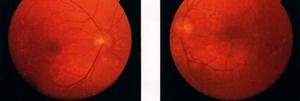

視盤玻璃膜疣表現為視盤上粗糙的、邊緣凹凸不平的、發亮的不規則結晶樣體,桑椹樣外觀,有些表現為假性視盤水腫。埋藏性玻璃疣由於玻璃疣位於視盤深部,眼底表現為視盤隆起,隨年齡增長,玻璃疣體積增大,可見性增加,埋藏性玻璃疣可以變為可見性玻璃疣。

表面玻璃疣的診斷並不困難,眼底表現為視盤上粗糙的、邊緣凹凸不平的、發亮的不規則結晶樣體,通常位於視盤的鼻側,有些表現為假性視盤水腫。埋藏性玻璃疣眼底表現視盤正常,或僅僅表現為視盤飽滿,需要B超、CT等輔助檢查才能診斷。